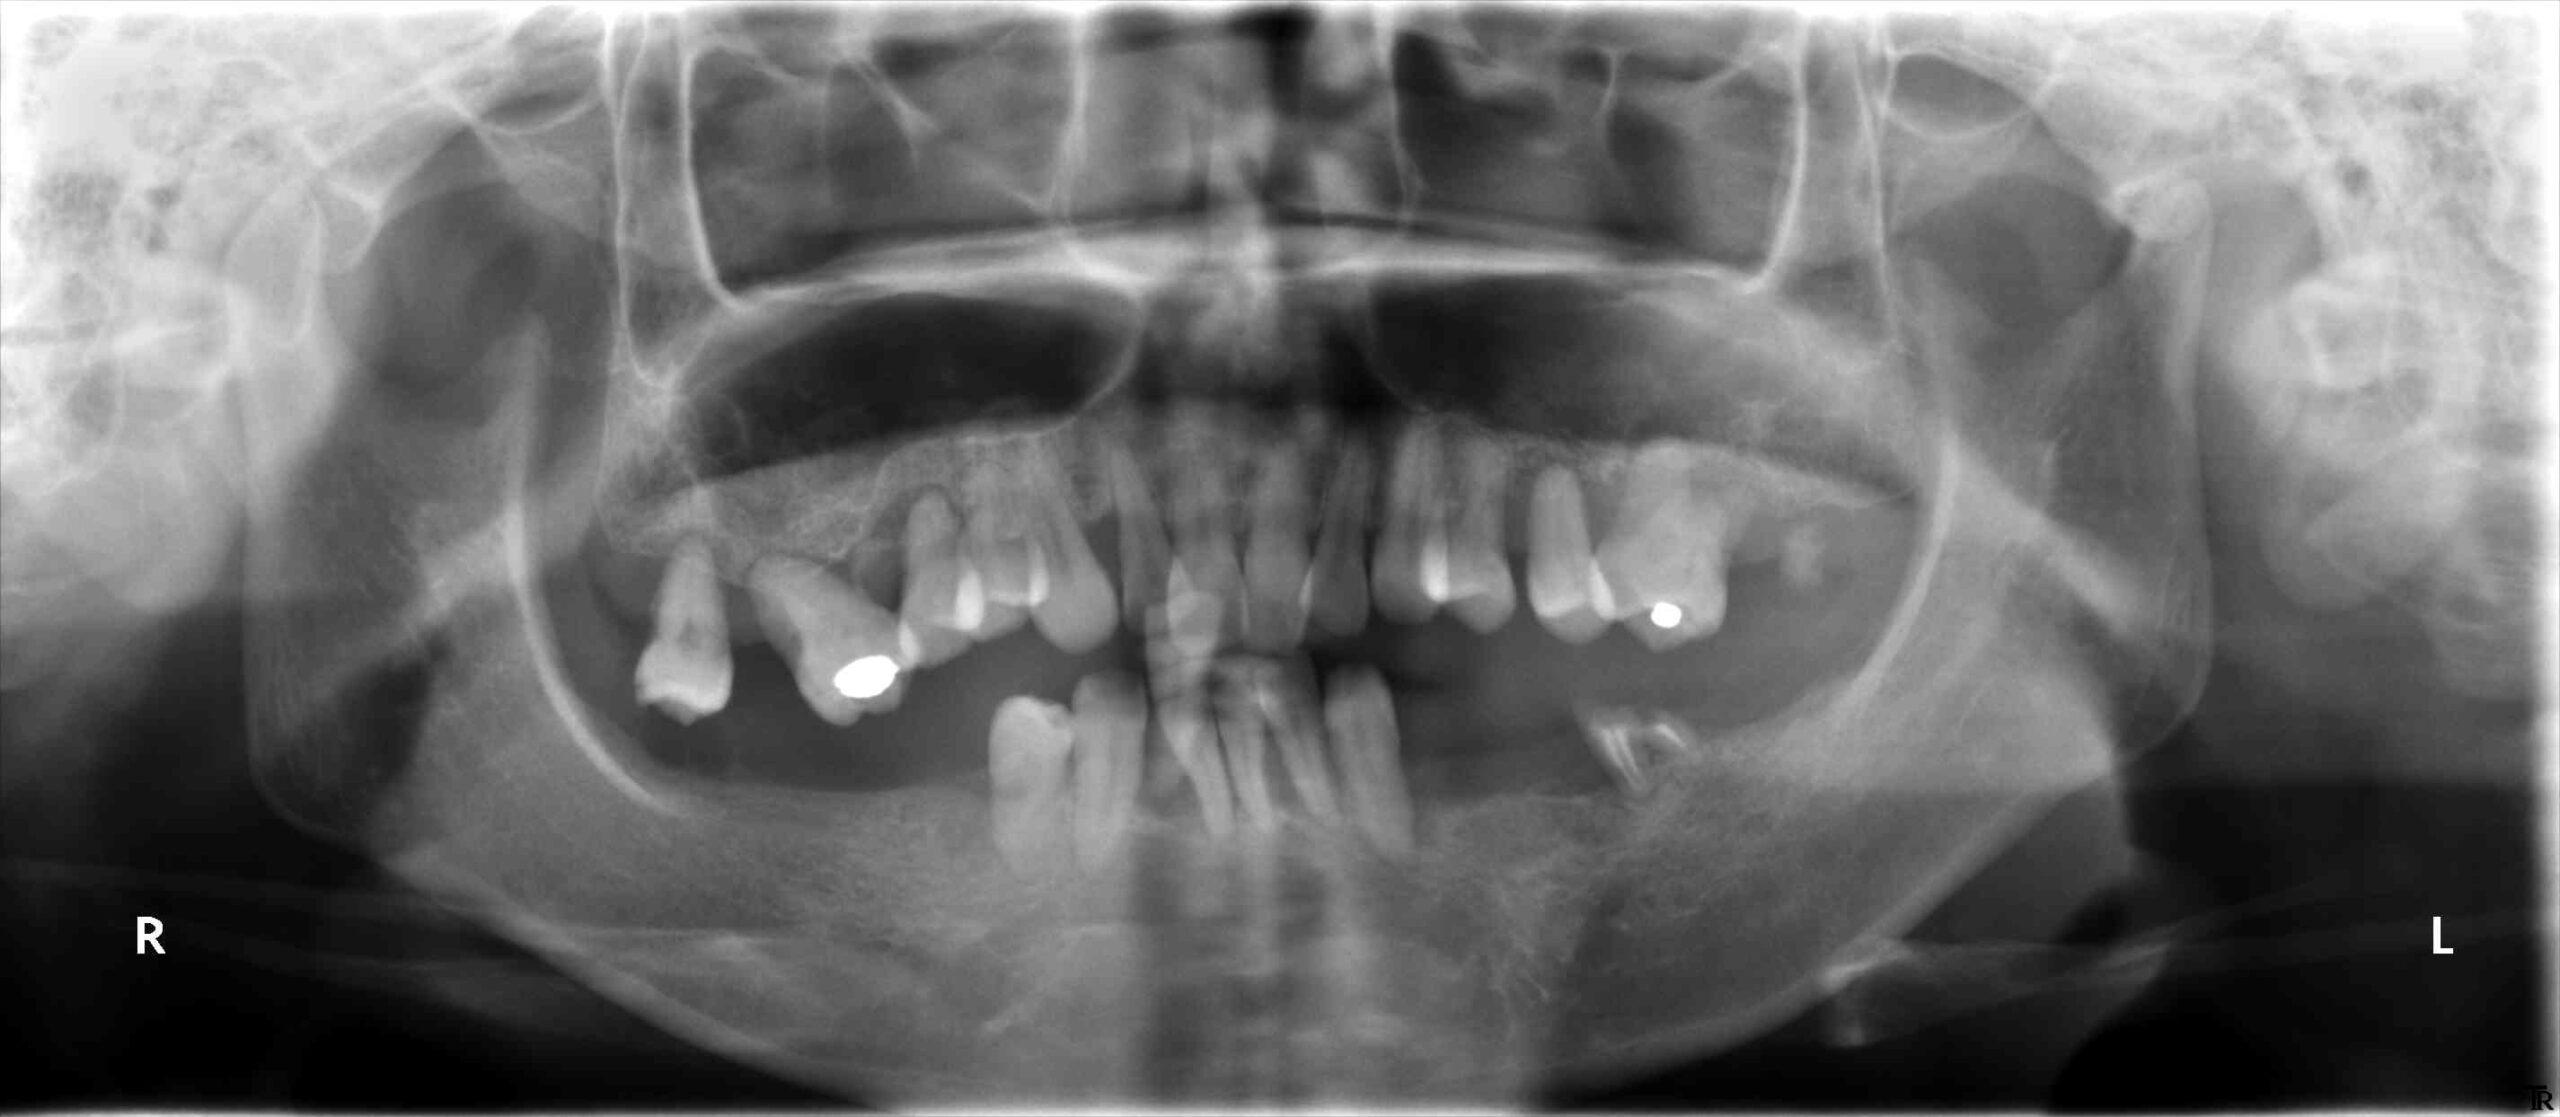

治療前のレントゲンです。

治療後は10本のインプラントで固定性の歯が得られています。